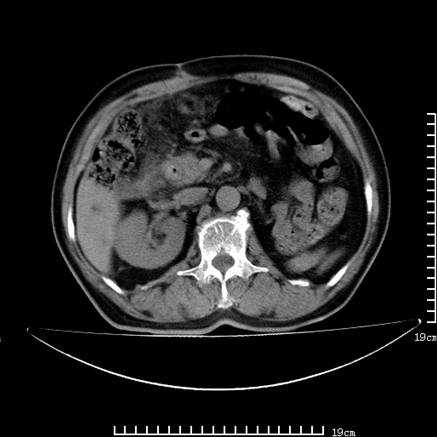

以下是引用lirenxiong在2008-7-19 22:01:00的发言:[br]胆总管结石并胆系感染,胆囊切除术后改变!左肾未见!左肾上腺增生肥大?请全腹扫描,增强!

以下是引用lirenxiong在2008-7-19 22:01:00的发言:[br]胆总管结石并胆系感染,胆囊切除术后改变!左肾未见!左肾上腺增生肥大?增强!